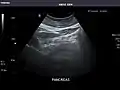

Spleen

Pancreas

Liver